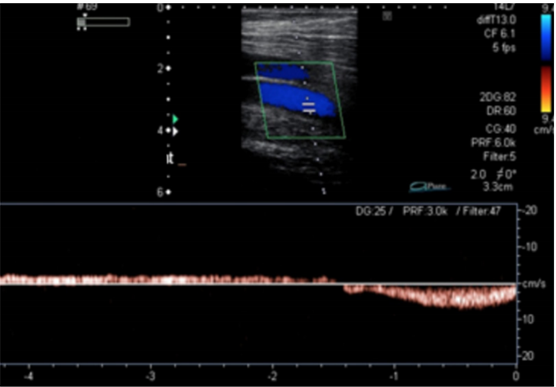

Paciente do sexo feminino, 65 anos, hipertensa, com queixa de dor e edema nos membros inferiores há cerca de 10 anos. Em consulta com o médico Cirurgião Vascular, foi solicitado exame ultrassonográfico com Doppler para mapeamento venoso dos membros inferiores. A imagem abaixo representa um segmento da veia femoral direita, durante manobra de aumento da pressão intra-abdominal e também em repouso (vide gráfico espectral).

Assinale a alternativa que contém o correto diagnóstico para este segmento venoso.